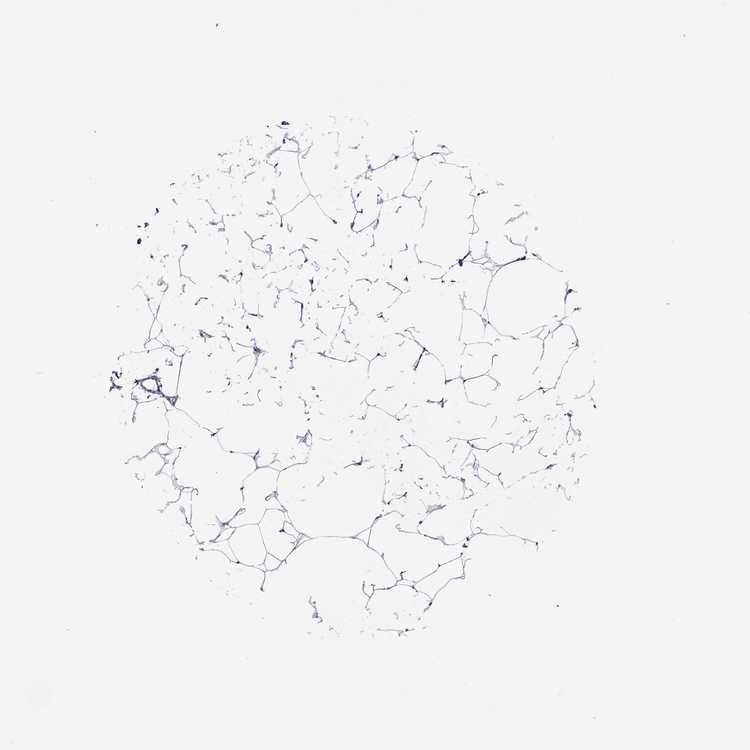

BREAST - Antibody stainingi

Antibody staining in the annotated cell types in the current human tissue is reported as not detected, low, medium, or high, based on conventional immunohistochemistry profiling in selected tissues. This score is based on the combination of the staining intensity and fraction of stained cells.

Each image is clickable and will lead to virtual microscopy that enables deeper exploration of all samples and also displays staining intensity scores, fraction scores and subcellular localization as well as patient and tissue information for each sample.

Antibody HPA004469

Adipocytes Not detected

Glandular cells Not detected

Myoepithelial cells Not detected